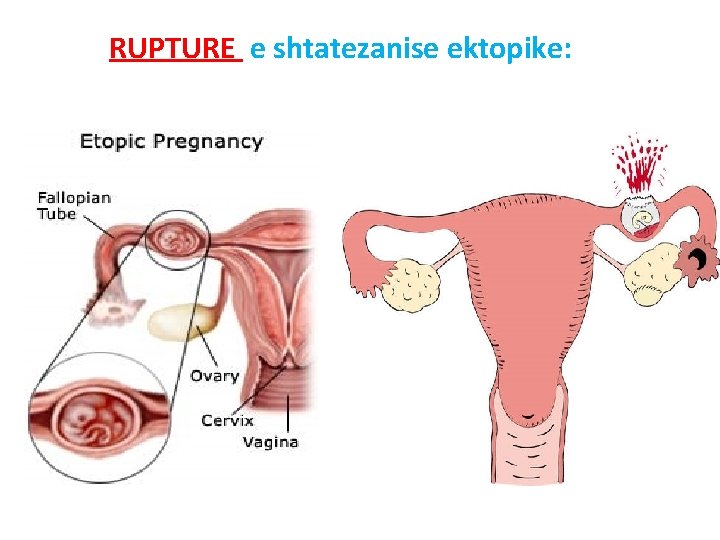

RUPTURE e shtatezanise ektopike:

• Cdo femer ne moshen e fertilitetit qe paraqitet ne urgjence me dhimbje te abdomenit te poshtem duhet te beje TESTIN E SHTATZANISE!!!!!!!